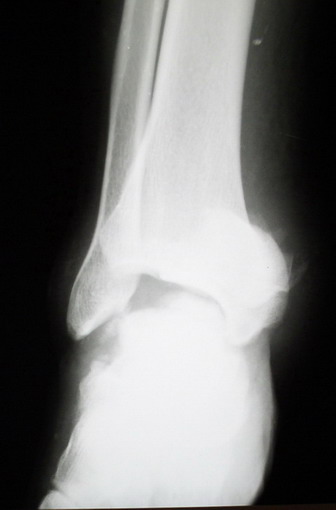

Глубокоуважаемые коллеги! Просим совета в лечении пациента с последствиями тяжелой сочетанной травмы. Пациент С., 41 года, по профессии бизнесмен, в сентябре 2005 г. пострадал в дорожно-транспортном происшествии (упал с мотоцикла). Диагноз: ЗЧМТ, ушиб головного мозга тяжелой степени. Открытый переломо-вывих левой таранной кости. Закрытые переломы лонной и седалищной костей слева. Был доставлен в НИИСП им. Н.В. Склифосовского. При ПХО раны выявлен открытый перелом левой таранной кости (III тип по Hawkins) с утратой вывихнутого тела таранной кости. Выполнена ПХО, фиксация голени и стопы стержневым аппаратом. Рана зажила без осложнений. Аппарат демонтирован через 1,5 месяца. В настоящее время больной предъявляет жалобы на боль в голеностопном суставе при нагрузке. Передвигается с опорой на костыли с дозированной нагрузкой на левую стопу.Голень и стопа фиксированы циркулярной пластиковой повязкой. Сохраняются остаточные явления ЧМТ (в виде сниженной критики к своему состоянию и определенной недисциплинированности в выполнении врачебных рекомендаций) Рентгенограммы – рис. 1, 2 (просим извинения за низкое качество рентгенограмм), схема – рис. 3. В качестве варианта хирургического лечения мы считаем возможным выполнить следующее вмешательство: артродез большеберцовой и пяточной костей в сочетании с артродезом переднего края большеберцовой кости и головки таранной кости с фиксацией спонгиозными винтами. Считаем выполнение артродеза переднего края большеберцовой кости и элементов I луча стопы необходимым для максимального восстановления опороспособности конечности. Однако выполнение операции в указанном объеме привело бы к относительному укорочению внутреннего свода стопы. Мы видим два пути решения данной проблемы: Вариант 1. Применение костного трансплантата (свободного или на сосудистой ножке) для замещения дефекта головки таранной кости и сохранения геометрии внутреннего свода стопы (рис 4). Преимущество: относительная простота операции. Недостаток: высокий риск замедленной консолидации или лизиса трансплантата. Вариант 2. Резекция участка пяточной кости с последующим остеосинтезом винтами для укорочения наружного свода стопы (рис 5, 6). Преимущества: сохранение собственного кровоснабжения всех синтезируемых участков костей. Недостатки: дополнительная травматизация, усугубление деформации стопы в виде нарушения наружного свода. Будем признательны за ваши предложения, включая возможные альтернативные варианты лечения.Заранее благодарны за добрые советы и поддержку. А. Федосов, О. Диденко, П. Иванов. Отделение множественной и сочетанной травмы НИИСП им. Н.В. Склифосовского, г. Москва.

> кости. Выполнена ПХО, фиксация голени и стопы стержневым аппаратом.

> Рана зажила без осложнений. Аппарат демонтирован через 1,5 месяца.